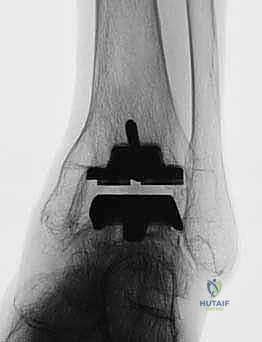

استبدال مفصل الكاحل الكلي بنظام TNK لعلاج خشونة الكاحل المتقدمة

استبدال مفصل الكاحل الكلي هو إجراء جراحي فعال يعالج خشونة الكاحل والتهاب المفاصل الروماتويدي في مراحلهما النهائية، باستخدام نظام TNK المبتكر لاستعادة وظيفة المفصل وتخفيف الألم بشكل دائم. يقدم الأستاذ الدكتور محمد هطيف هذا العلاج المتطور في صنعاء، مع التركيز على التخطيط الدقيق والتقنيات الجراحية المتقدمة لضمان أفضل النتائج للمرضى.

الخلاصة الطبية الشاملة: يُعد استبدال مفصل الكاحل الكلي (Total Ankle Arthroplasty - TAA) ثورة طبية حقيقية وإجراءً جراحياً بالغ الفعالية لعلاج حالات خشونة الكاحل المتقدمة والتهاب المفاصل الروماتويدي في مراحلها النهائية. من خلال استخدام نظام TNK المبتكر، يتم استعادة الوظيفة الحركية للمفصل وتخفيف الألم المزمن بشكل دائم، مما يعيد للمريض جودة حياته المفقودة. يقود هذا التطور الطبي في اليمن الأستاذ الدكتور محمد هطيف، أستاذ جراحة العظام والمفاصل بجامعة صنعاء، والذي يمتلك خبرة تتجاوز 20 عاماً. يرتكز الدكتور هطيف في ممارسته على الأمانة الطبية الصارمة، والتخطيط الجراحي الدقيق، مستخدماً أحدث التقنيات العالمية مثل الجراحة الميكروسكوبية، ومناظير المفاصل بتقنية 4K، والمفاصل الصناعية الحديثة لضمان تحقيق أعلى نسب النجاح العالمية لمرضاه في صنعاء.

لماذا نظام TNK؟ ثورة في المفاصل الصناعية

يُعد اختيار نوع المفصل الصناعي قراراً حاسماً. يفضل الأستاذ الدكتور محمد هطيف استخدام نظام TNK (وأنظمة مشابهة من الجيل الحديث) لعدة أسباب علمية وهندسية قوية:

- التثبيت بدون أسمنت عظمي (Cementless Fixation): تعتمد مكونات نظام TNK على طلاء خاص (غالباً من التيتانيوم المسامي أو الهيدروكسي أباتيت) يسمح للعظم الطبيعي بالنمو والاندماج المباشر مع المعدن (Osseointegration). هذا يوفر تثبيتاً بيولوجياً قوياً وطويل الأمد يقلل من احتمالية تخلخل المفصل بمرور الوقت.

- تصميم يحاكي التشريح (Anatomic Design): كما ذكرنا سابقاً، الميلان الخلفي بمقدار 10 درجات في المكون الظنبوبي يعكس التشريح الطبيعي بدقة، مما يحسن من استقرار المفصل ونطاق حركته.

- مواد عالية التحمل: يتكون المفصل من سبائك معدنية فائقة القوة (مثل الكوبالت كروم أو التيتانيوم) مع حشوة بلاستيكية طبية متطورة (Highly Cross-linked Polyethylene) تقاوم التآكل بشكل استثنائي.

5. زراعة نظام TNK النهائي

بمجرد التأكد من المقاسات والزوايا المثالية، يتم زرع المكونات النهائية. يتم إدخال المكون الظنبوبي المعدني بقوة ليثبت في العظم، يليه المكون الكاحلي. أخيراً، يتم إدخال الح